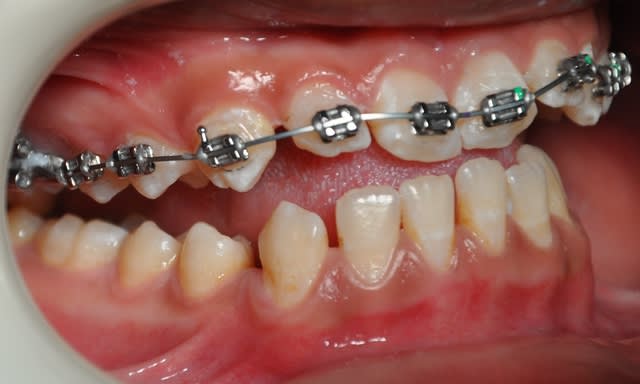

2ème étape

Dsc 0004 lwlouj - Eugenol

Dsc 0003 kobtob - Eugenol

Dsc 0005 pfdneo - Eugenol

Dsc 0006 pndvvp - Eugenol

Dsc 0001 hztqqg - Eugenol

Dsc 0002 b3d098 - Eugenol